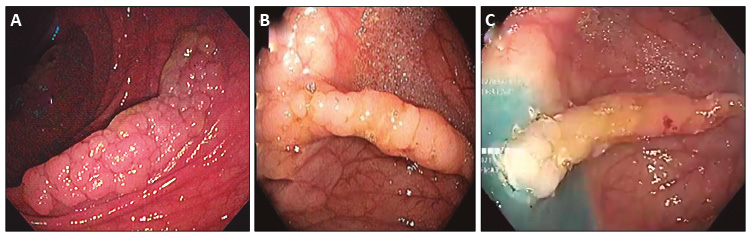

Se le realizó una REM en fragmentos por no obtener una buena elevación mucosa (Figura 3 A y B).

El resultado de la anatomía patológica de los fragmentos recuperados informó un adenoma tubulovelloso con una displasia de bajo grado con los márgenes de resección comprometidos.

Se le realizó un nuevo intento de tratamiento endoscópico a los 4 meses con el objetivo de evitar una cirugía. La falta de elevación de la mucosa por fibrosis en un extremo fue un criterio de irresecabilidad para técnicas convencionales, motivo por el cual se procedió a la EFTR (Figuras 3 C y 4).

El clip cerró el sitio de la resección de manera eficiente, pudiéndose observar del lado intraluminal los bordes del peritoneo sujetos (Figura 5 A).